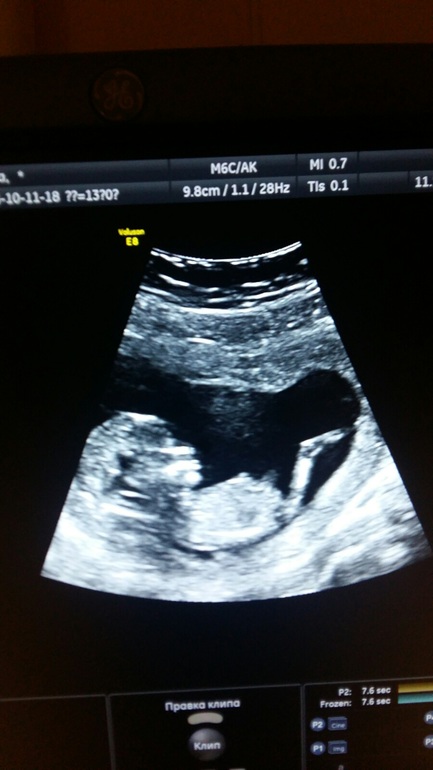

УЗИ, КТГ, доплерВот так выглядит чудо которое ждали 8 лет!!!!))) Как сказала моя подружка, профиль как у фараона😂

Слышала, что как то на таких сроках можно определить пол. Хотя мой УЗИст посмеялся)))

Ух ты, класс!! Реально на фараона похож)))) милаха))для пола конечно рановато))) через недельки две-три уже можно узнать в 16-17 недель))) подушка классная, и спину подпирает, и ногу закидываешь,правда жарковато в ней)))) у меня такой же формы, вообще не могла без нее спать ))

Такой классный,губки выпятил так)))

Красота то какая!!!!! Я знаю ты мальчика хочешь,его и желаю тебе..но главное здоровье обоих!!!! Ммммм любо дорого смотреть на них)))))) и ни какой ни фараон... Просто не понравилось что светят на него рахглядывают))))